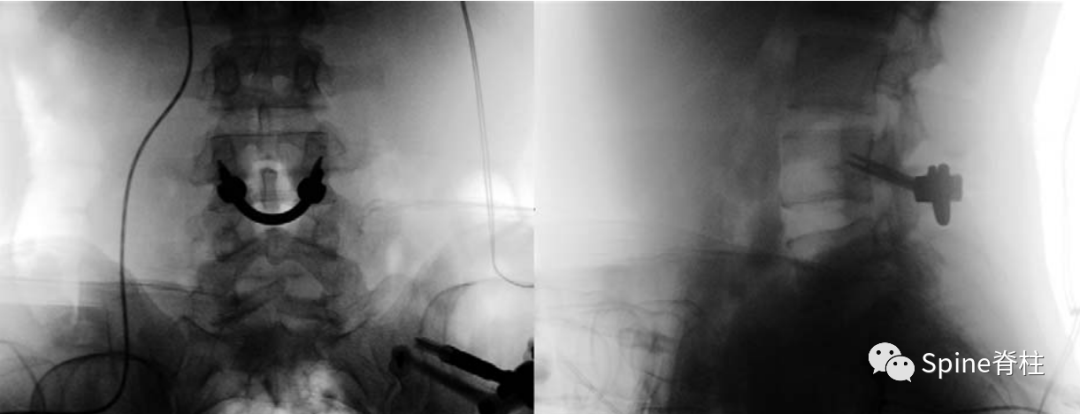

2. 椎弓根螺钉+U型或V型棒

U型棒

• V型棒 PMID: 10382254

V型棒 (PMID: 23691090)